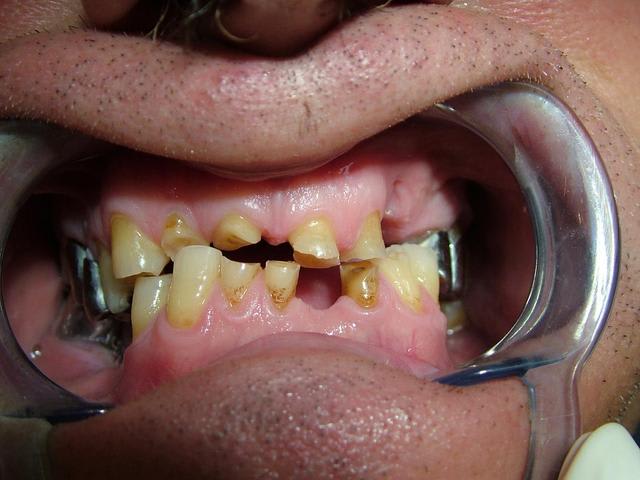

Contrairement à ce qui a été dit...Il n'y a pas de perte de Dimension verticale. Les secteurs posterieurs sont plus ou moins preservés

(couronne métallique..)

Par contre dans le secteur anterieur l'usure des dents à été compensé par une egression qui donne l'illusion de perte de DV...

Le traitement est complexe car on peut pas vraiment augmenter la DV...il y pas ou peu de perte. Si on surevalue la DV, ça peut etre super mal toléré.

tu les trouves égressées toi les incisives inférieures?

Oui...egressé et usée. Regarde l'os alveolaire de la pano.

L'idée de cingulum me semble la plus acceptable car il y a néanmoins un calage postérieur qui a sans doute permis de conserver la DV d'origine ou du moins éviter qu'il y ait un effondrement important. La remarque de cingulum me semble particulièrement pertinente.

Merci pour toutes les réponses qui m'ont aidé à réfléchir au cas et surtout ne pas me précipiter sur mon plan de traitement stupidement. J'ai revu le patient il y a qq jours et je devais ce jour là lui faire la présentation du plan de traitement. Je lui ai expliqué que son cas était tellment complexe que je n'avais pas pour le moment de solution thérapeutique valable car je n'avais pas encore traité ce type de cas. Le patient a fort bien compris et j'en ai profité pour prendre des radios buccales ; en effet la mise sur occluseur que j'avais sur les précédentes photos était fausse. Le patient "occluse" différement. Voir les nouvelles photos jointes. Il y a très peu de contact antérieur ; j'ai bien demandé une dizaine de fois au patient de se mettre en occlusion pour arriver au même résultat que l'on voit sur les photos. Le patient a bien sur du mal à avoir un occlusion stable.

Ce qui m'interroge le plus c'est comment ce patient est arriver à user le bloc antérieur et arriver à cette situation. Il n'a pas d'habitudes nocives ( ex fumeur de pipes ou autres tics).

Il est vrai que la DV me semble conservé car il y a un calage postérieur côté droit et côté gauche.